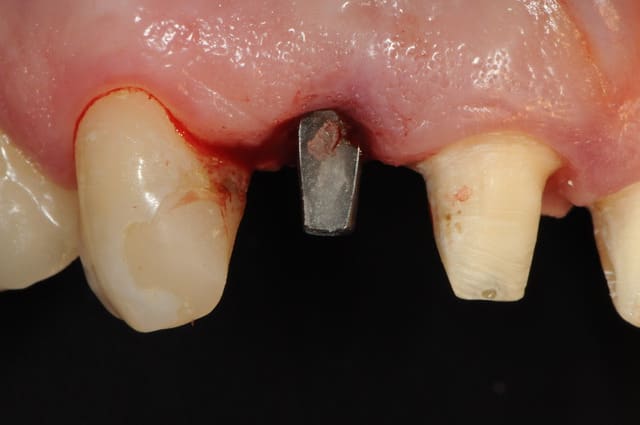

donc après encore 3 mois, je fais enfin la mise à jour de l'implant (un vrai bonheur avec ce système implantaire où l'on vient chercher la vis de couverture "à l'aveugle")

photo 8 : provisoire réalisée à partir d'un moule Ion

photo 9-10 : positionnement de la dent

"Une petite question : comment as tu déterminé la profondeur d'enfouissement de l'implant ? il est enfoui de combien de mm sous le niveau osseux ?"

je m'arrange pour que le bord périphérique du pilier soit 1 à 2mm sous le contour gingivale des dents voisines. cela suppose qu'il faille essayer le pilier idéal PENDANT la chirurgie. il en faut donc plusieurs, mais c'est là l'avantage de poser soit même ses implants car on a l'habitude de faire la prothèse aussi. ce n'est donc pas le cas des stomato à qui je reprocherai simplement le manque d'expérience en prothèse. quand je pose un implant pour un correspondant, il ne lui reste quasi plus rien à faire, même le choix du pilier le plus approprié est défini à l'avance. généralement, il est rare que l'on doive changer de référence.